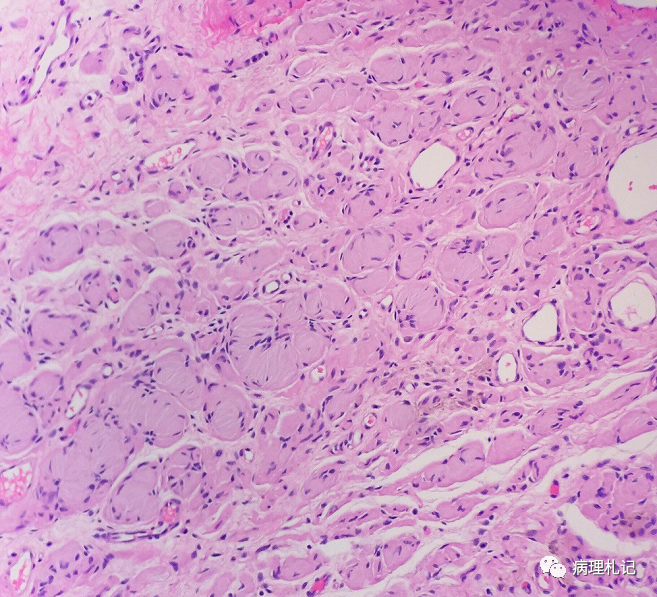

弥漫性神经纤维瘤中惊叹wagnermeissner小体